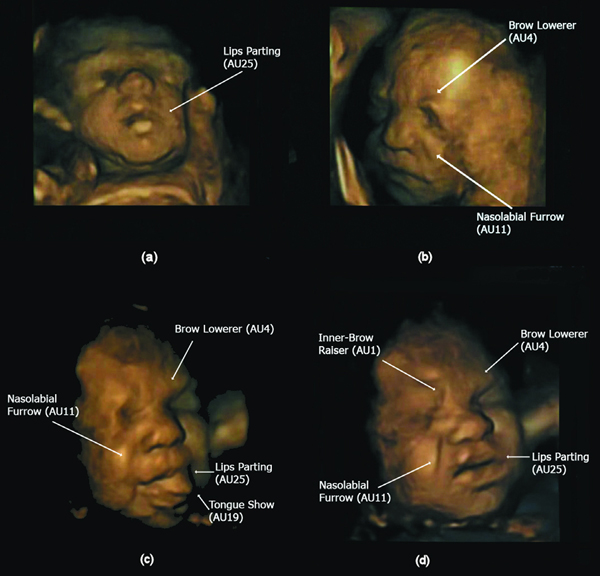

Figure 1. Illustration of developmental progression in number of action units (AUs) over gestational age. (a) One AU at 24 weeks (b) Two AUs at 27.5 weeks (c) and (d) two different combinations of 4 AUs at 32 weeks. doi:10.1371/journal.pone.0024081.g001

The scans were made in the second and third trimester. The researchers found that between 24 and 35 weeks, the occurrence of 3 or more facial movements increased from 7-69%. Also, recognizable facial movements were discernible, rising from 0% to 42%. This led to specific facial expressions increasing from 0-35%. The frequency with which the changes occurred also increased with age.

The present study confirms that over the second to third trimester fetuses develop a large amount of facial action units producing movements that near emotional expressions including those found in the cry and laugh face.

The complexity of the movements also increased over time.